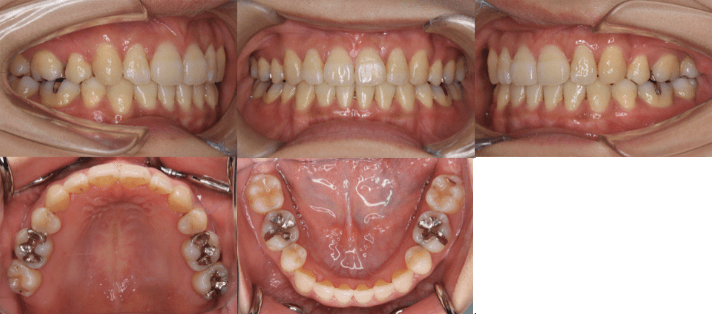

治療後

• 初診時年齢:25歳7ヶ月

• 主訴:前歯のガタガタ

• 診断:交叉咬合を伴う叢生症例

• 治療内容:小臼歯4本を抜歯した後、マウスピース型カスタムメイド矯正歯科装置(製品名インビザライン 完成物薬機法対象外)を使用して主訴である叢生の改善を行いました。

• 治療期間:2年

• リスク:矯正治療による歯の移動に伴う痛み、歯根吸収、虫歯

• 費用:80万円